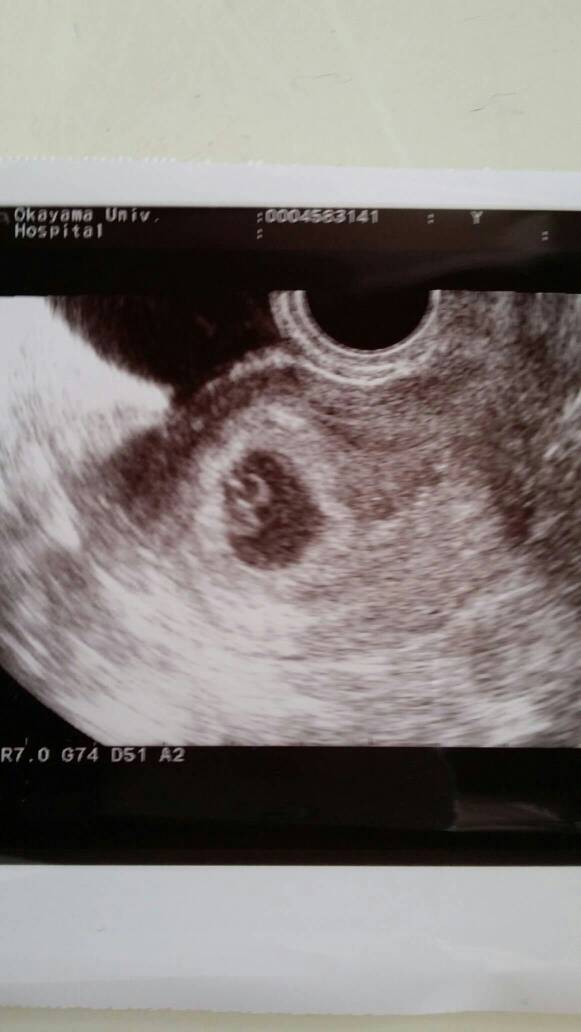

在同一个卵泡腔有两个胚胎在发育,一般来说就是同卵了。异卵的话会出现两个卵泡腔的。你的情况只有一个,应该是同卵。

应该是双胞胎,估计是同卵的。异卵是不同的精子和不同的卵子结合所以在子宫着床的部位也是不同的

从我这个角度看还是很有可能是两个的。还是怕拍摄角度的问题,没有100%的答案医院也是不敢确定的。至于健康的有可能把另一个吸收,这种说法不科学,胚胎的发育营养来源主要还是母体,只有可能两个胚胎相互竞争吸收营养,可能会导致另一个发育不太好吧!也有可能同卵的胚胎的有一个在发育的过程中自身问题而凋谢。